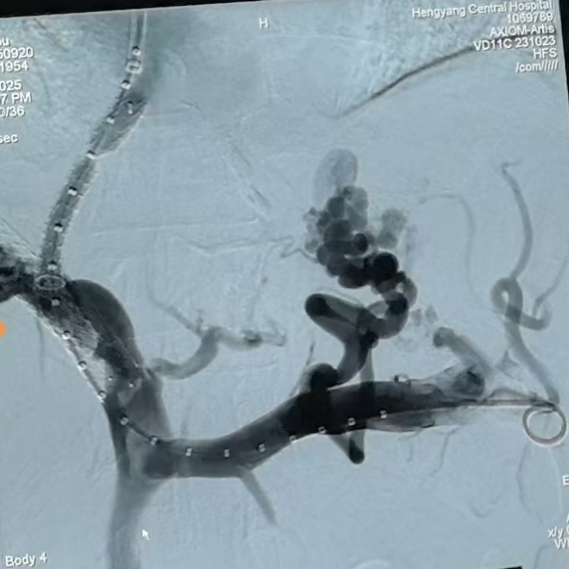

圖一:TIPS術中

第三步,手術實施與術后管理。9月20日,在消化介入團隊精湛操作下,成功為患者實施TIPS支架修補術。術中,團隊克服了患者肝內血管結構因既往手術和肝硬化而異常復雜等諸多困難,精準地在門靜脈與肝靜脈之間建立了有效分流,并置入覆膜支架以確保分流道長期通暢。術后門靜脈壓力即刻顯著下降,達到了預期血流動力學目標。

圖二:TIPS術中影像